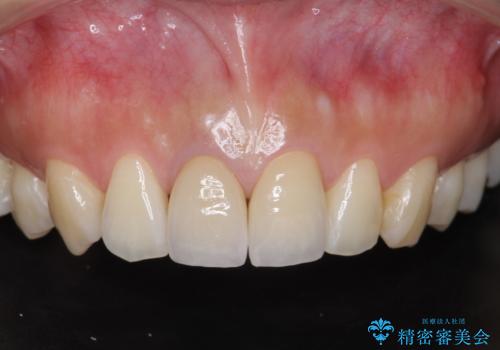

前歯の変色 根管治療と高品質セラミック歯科治療

前歯をメタルフリーに 根管治療で不安を取り除いてから

上の前歯の根元が黒い 根の治療を含めたセラミック再治療